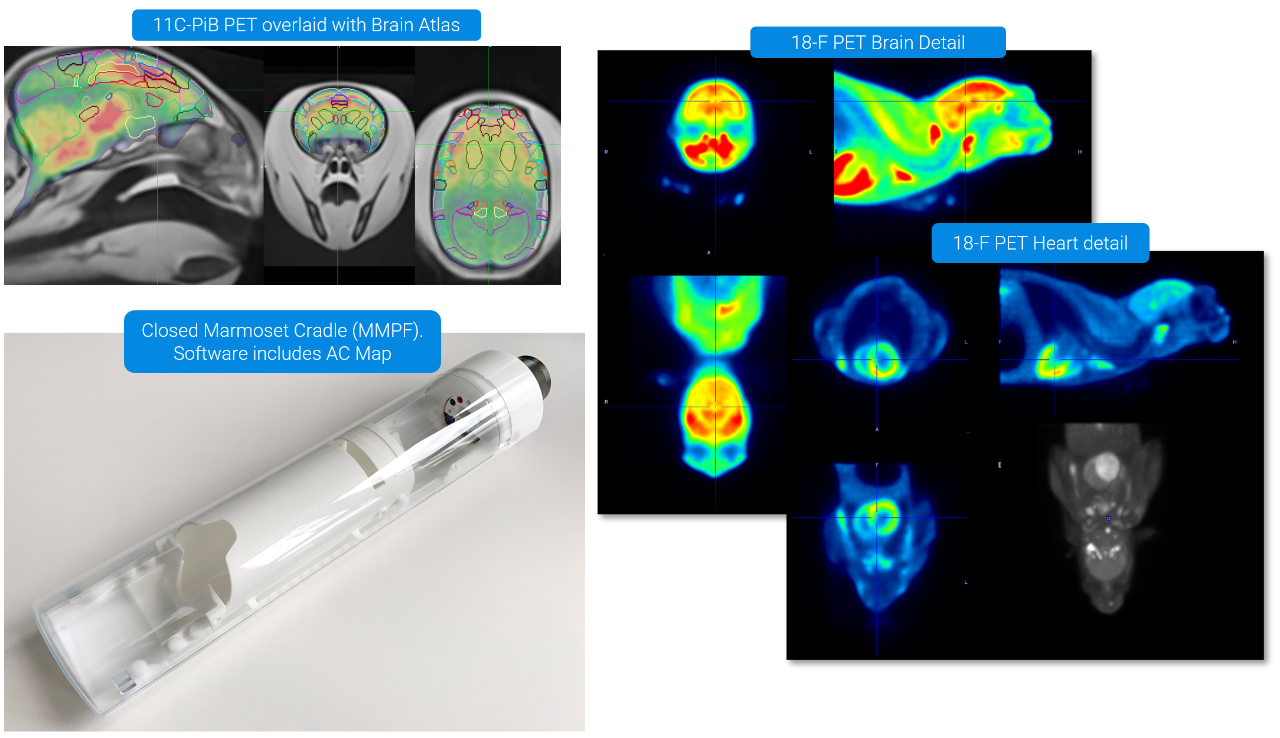

The PET/CT Si78 is a high throughput imaging instrument, dedicated for drug and tracer development for clinical translation . It combines highest PET sensitivity with fast and low dose CT.

The PET/CT Si78 is a molecular imaging system for sequential Positron Emission Tomography (PET) and X-Ray Microtomography (uCT). The fully shielded scanner, the animal welfare solutions and the experimental workflows are designed to support high throughput translational preclinical research in all field s of nuclear molecular imaging research.

ParaVision 360 software offers the complete solutions from subject & study handling, to scan execution, image reconstruction co-registration & image fusion, data analysis and automatic report generation. It easily links imaging data to the most advanced quantitative PET data analysis and kinetic modelling features offered by the PMOD biomedical image quantification software of Bruker.

• PMOD software tools for advanced data analysis and quantification

• Up to 0.7 mm spatial resolution

• Up to 12 % sensitivity

• 150 x 80 mm FOV

• True DOI, no loss of resolution across FOV

• Ultrafast GPU reconstruction (MLEM, OSEM and MAP)